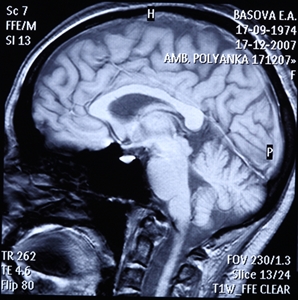

According to a report from NPR, the first lobotomy was performed in the U.S. in 1936, and gained popularity in the 1940s. Many doctors thought the procedure, which severs connections in the brain, would eliminate emotions and help stabilize moods, especially in those who had schizophrenia or symptoms of depression and anxiety.